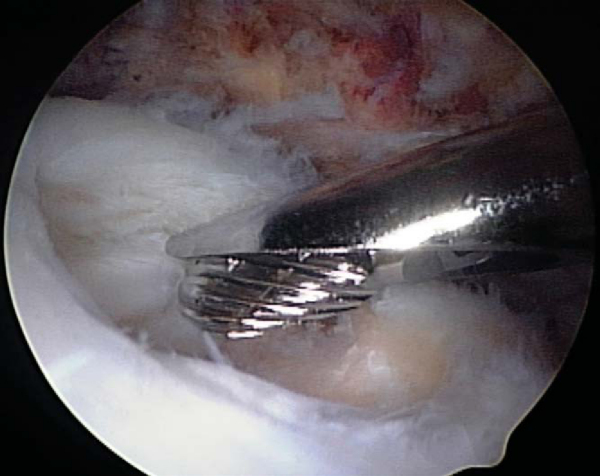

Side-to-side repairs are performed in a medial to lateral progression with free sutures that can be passed through the tendon substance by a variety of instruments and techniques (

Fig. 16-6

). Our preference is to use a straight penetrating suture grasper when working in the posterior two thirds of the cuff as well as during repair of the more medial extent of the side-to-side component of a tear. Laterally and anteriorly, a shuttle-type suture-passing device is more effective. Sutures should generally be tied directly after passing and before anchor placement to reduce the risk of suture entanglement (

Fig. 16-7

).